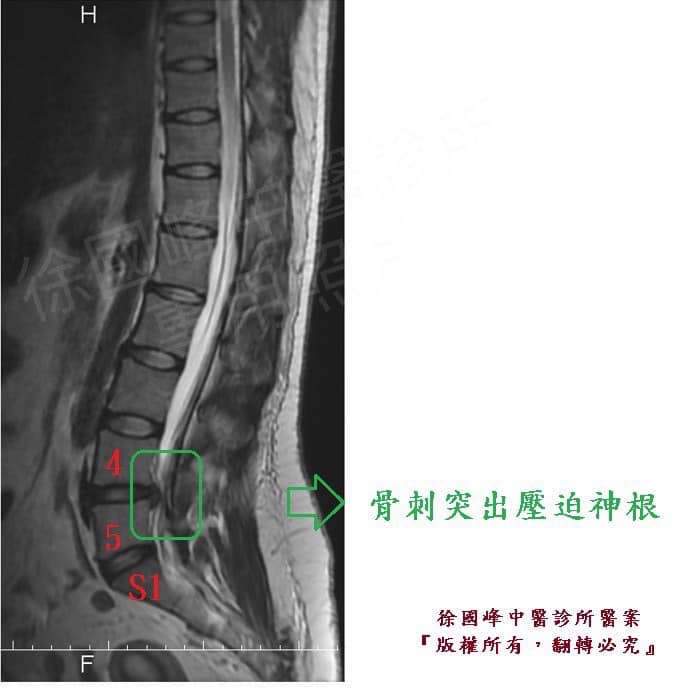

1.左側L4L5 纖維環出現輕微裂隙TAPE 3A合併HIVD